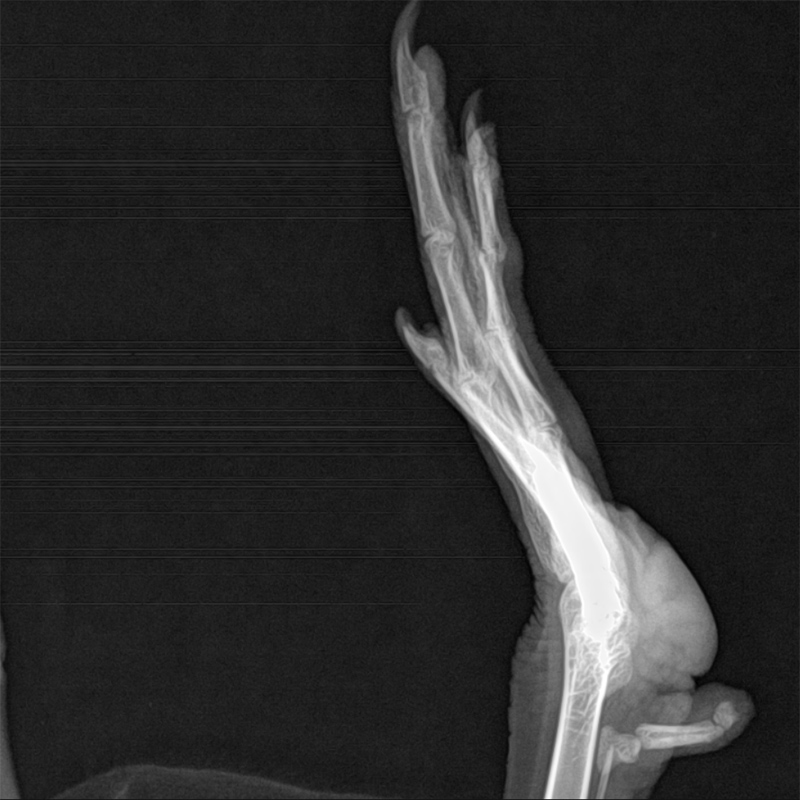

Do Ducks Have Knees? Duck Leg Anatomy Explained Farmhouse Guide Normal Duck Foot Vs Bumblefoot Bumblefoot refers to an inflammatory condition caused by bacteria (like strains of escherichia coli, staphylococcus & pseudomonas). Look for localized redness and inflammation around the footpad, especially near cuts or punctures. That very first photo looked like early bumblefoot. Along with swelling, the infected area is often easily. Here’s how to spot the telltale signs of bumblefoot in ducks: Bumblefoot. Normal Duck Foot Vs Bumblefoot.